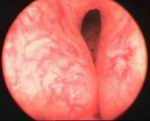

Prostatic enlargement is a comman problem is old age. By TURP nearly all patient who requires surgery for prostate can be treated successfully without any incision. Under anesthesia per urethral scope is inserted & under vision prostate is resected. Patient requires 2 to 4 days hospitalization & 1 week rest. Usually patient does not requires blood transfusion & patient can tolerate endoscopic surgery very well without risk of incontinance of urine.